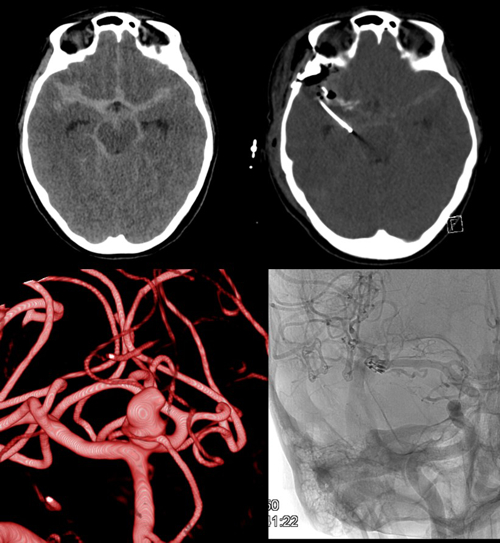

In addition to the continual prospective analysis of treatment results of vascular pathologies (e.g. aneurysms, arteriovenous malformations, arteriovenous fistulas, intracerebral haematomas and strokes etc.) and constant improvements in technical standards, adjuncts and operative techniques, the use of advanced imaging along with various biomarkers is being investigated, in order to have a beneficial influence on patient treatment and neurological outcome.

Severe head injury and aneurysmal SAH (Fig. 4) as well as haemorrhagic strokes are common medical conditions in the department. As well as multimodal monitoring and numerous pathophysiological investigations, various multi and monocentric studies are regularly undertaken. Invasive multimodal neuromonitoring of brain oxygenation, metabolism, blood flow and intracranial pressure alongside advanced imaging and targeted metabolomic profiling are performed for continuous evaluation of these techniques in treatment optimisation and patient outcome after subarachnoid haemorrhage and severe/moderate head trauma.

- Dual ICP: Simultaneous application of multimodal invasive neuromonitoring in both intracranial supra/infratentorial compartments of patients with posterior fossa lesions, to obtain additional comprehensive data from the entire brain.

- NICAPLANT: Phase-IIb trial of nicardipine prolonged release pellets in aneurysmatic subarachnoid haemorrhage.

- TIBI I/II: Multimodal invasive neuromonitoring in patients with severe and moderate head trauma in combination with early MRI and targeted metabolomics, identifying CFS and serum biomarkers of neuronal injury.

- PREVAIL: Pilot trial of autologous intravenous CSF transfusion for the prevention of cerebral vasospasm after SAH.

- Cerebral vasospasm and delayed cerebral ischaemia after aneurysmal SAH – European / North American surveys and transnational cohort studies.